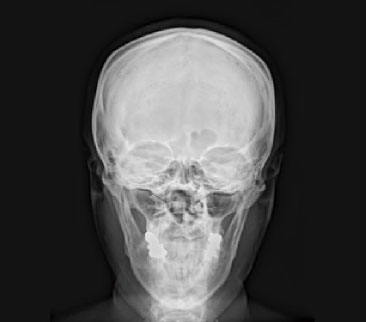

一般撮影

一般撮影とは

一般撮影は、レントゲン検査やⅩ線撮影と呼ばれることもあり、胸部、腹部、骨など全身各部位の撮影を行います。

Ⅹ線という放射線を人体に照射して透過したⅩ線を画像にします。

検査時間は、部位や撮影回数により異なりますが5~10分程度です。

頭部